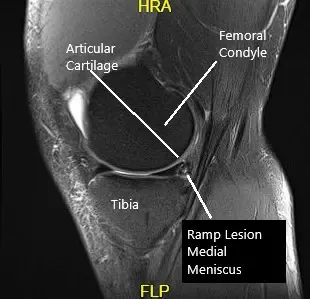

MRI examination of the left knee suggested a complex tear of the posterior horn of the medial meniscus. Small horizontal cleavage tear of the body of the lateral meniscus.Moderate joint effusion with synovitis.

MRI of the knee in the sagittal and coronal section.